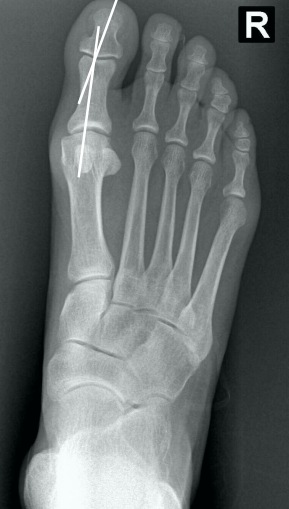

• Na avaliação radiográfica em AP com carga, quais os principais ângulos a serem traçados?

• Ângulo de valgismo do hálux (metatarsofalângico)

• Ângulo intermetatarsal

• Ângulo de valgismo interfalângico do hálux

• Ângulo articular metatarsal distal (AAMD)

• Na radiografia em AP com carga, como é traçado o ângulo intermetatarsal?

• Ângulo entre o eixo longo do 1° e do 2° raio

• Normal → até 9°

• Leve → 9° a 12°

• Moderado → 13° a 15°

• Grave → > 16°

• Na radiografia em AP com carga, como é traçado o ângulo de valgismo do hálux (metatarsofalângico)?

• Ângulo entre o eixo longo do 1° mtt e o eixo longo da falange proximal

• Normal → até 15°

• Leve → < 25°

• Moderado → 25° a 40°

• Grave → > 40°

• Na radiografia em AP com carga, como é traçado o ângulo de valgismo interfalângico do hálux?

• Ângulo entre o eixo longo da falange proximal e o eixo longo da falange distal

• Normal → até 10°

• Na radiografia em AP com carga, como é traçado o ângulo articular metatarsal distal (AAMD)?

• Traça-se uma linha unindo os dois pontos mais largos da superfície articular do 1° mtt e outra linha perpendicular a esta

• Depois, traça-se uma linha no eixo longo do 1° mtt

• O ângulo entre as duas maiores retas → até 15°